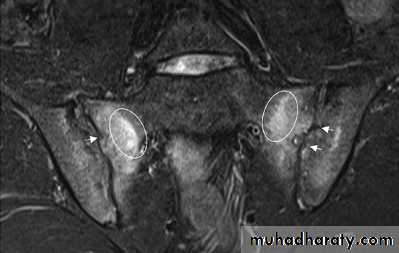

Patients with early disease can have normal Xrays, and if clinical suspicion is high, MRI should be performed. This is much more sensitive for detection of early sacroiliitis than Xray and can also detect inflammatory changes in the lumbar spine.